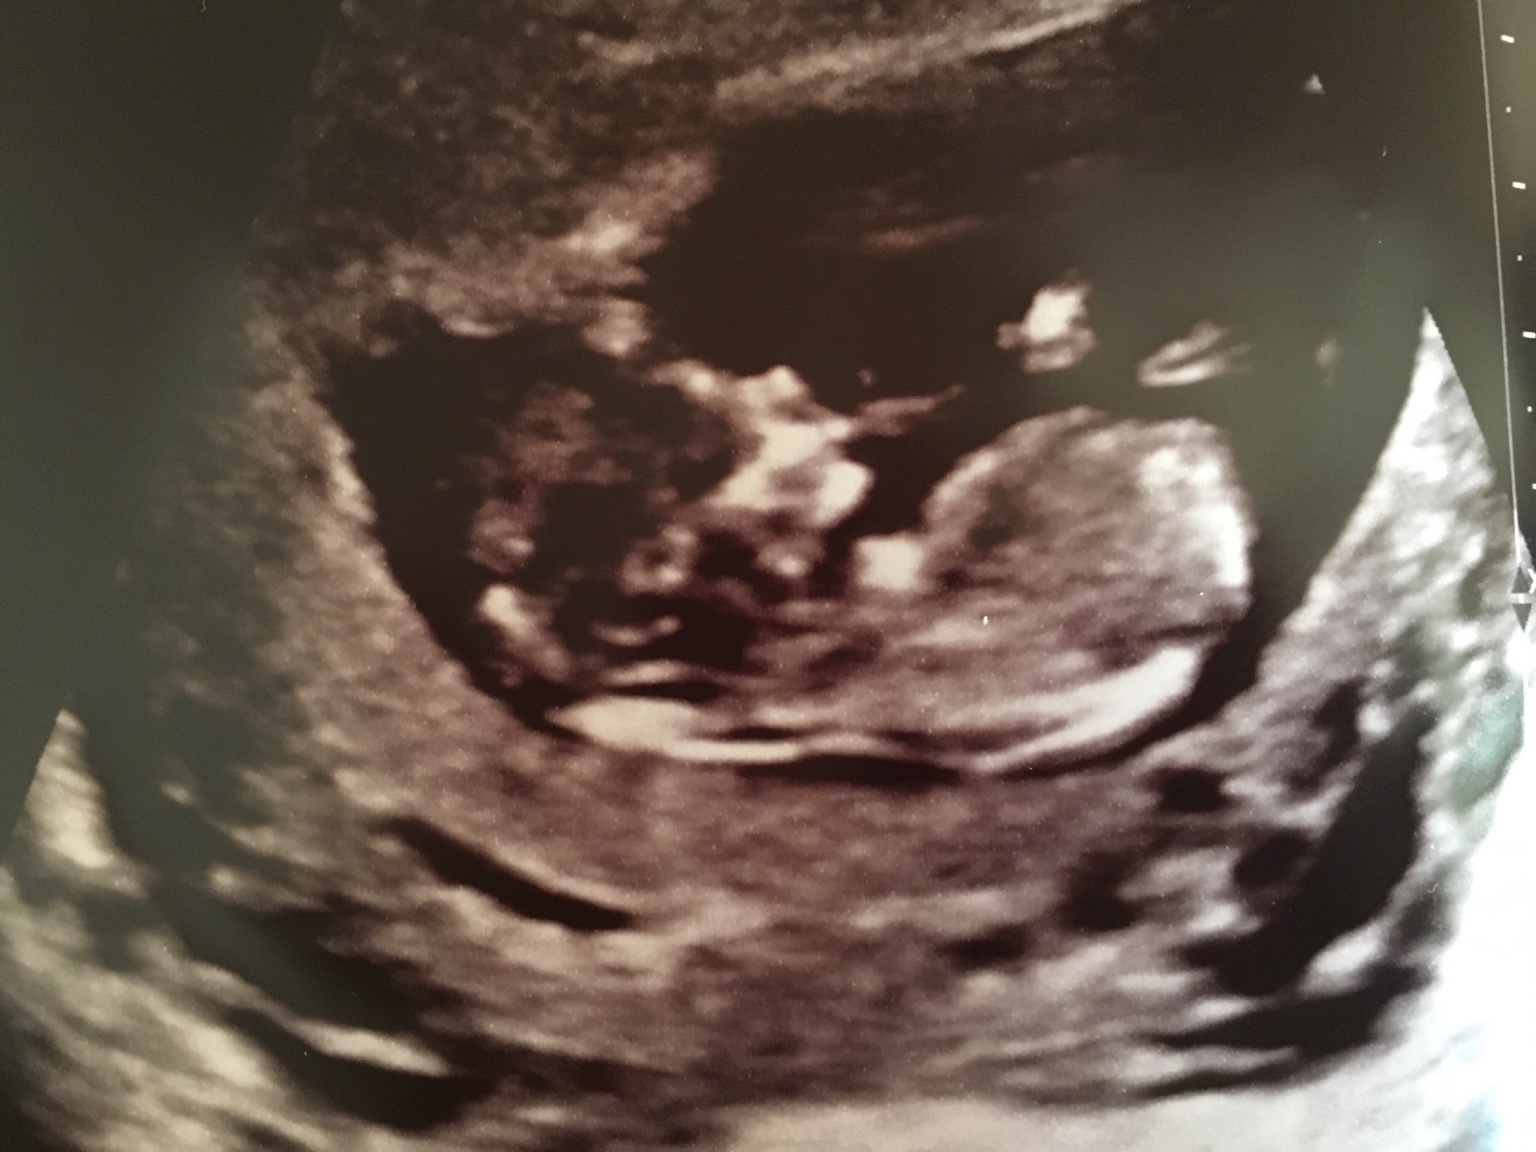

Please help me in guessing the gender. Attachment 28542

Here are some more shots any chances of a girl or having a girl will be in my dreams only now [emoji26][emoji26]Attachment 28562Attachment 28563

Possibly blue if thats the nub but there is so much detail missine ie legs, cord?? The bit on the end could be anything as we cant see where the other bits are! so def do not lose hope off of this pic GL:)

The 12 week scan is from 12+0 to 12+6. The best for nubs is 12+3 and upwards. 13+0 to 13+6 is even more reliable. How far along were you here exactly? In any case, if it's looking boyish at 12 weeks it won't be looking girly later on, only the other way around (looking first girly in week 11-12 and then boyish in week 12-13). I hope we're wrong about it being a boy, but I've been there and have heard DS2 and DS3, you'll be ok.

I would guess boy from the first picture.